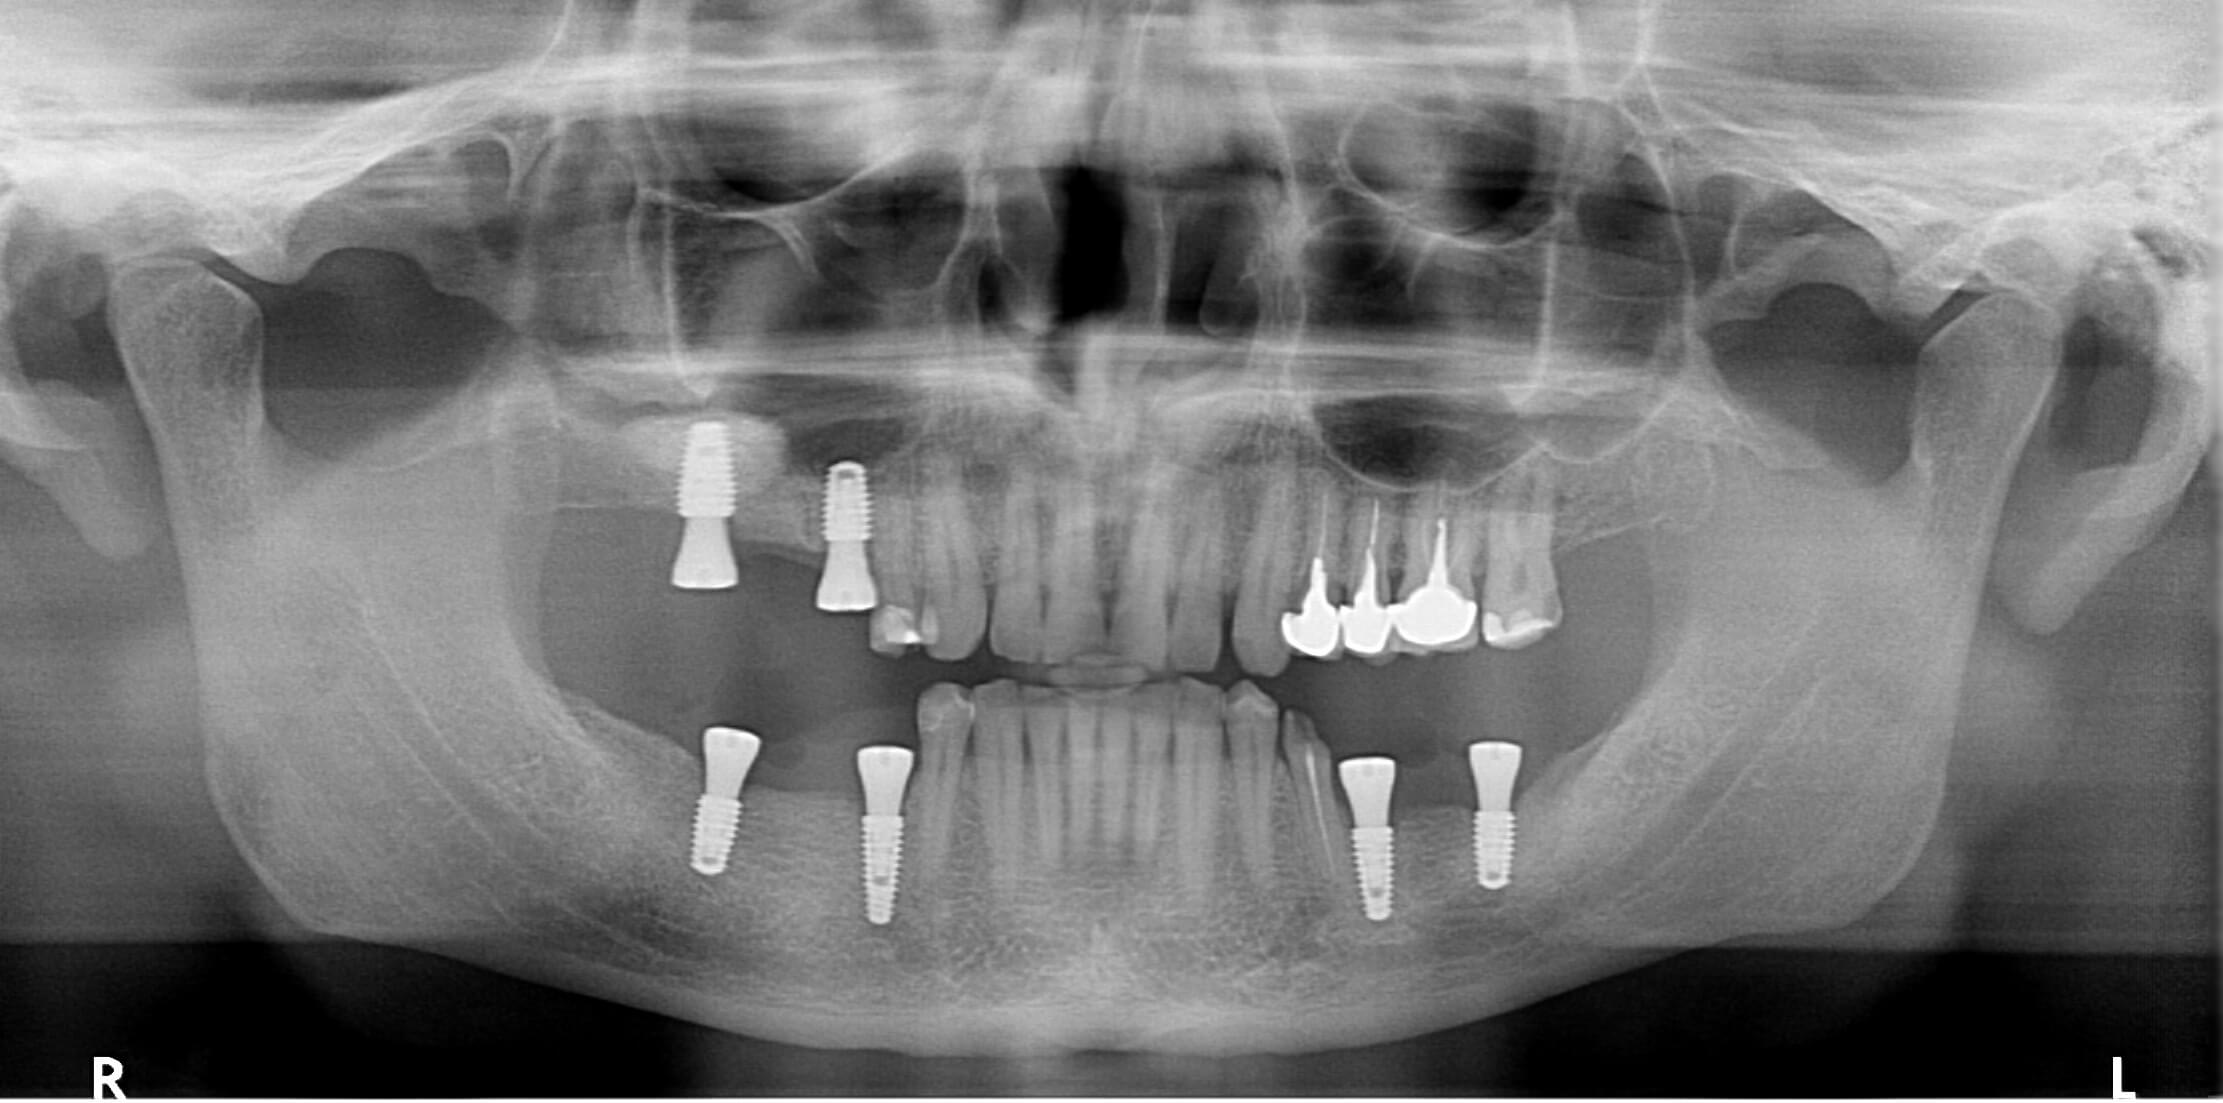

На первом этапе было проведено наращивание костной ткани на верхней челюсти (синус-лифтинг), одновременно с этим были установлены имплантаты, а также проведена пластика мягких тканей.

Ровно через 4 месяца было проведено протезирование боковых отделов циркониевыми коронками, а также мостовидными протезами с опорой на имплантатах.